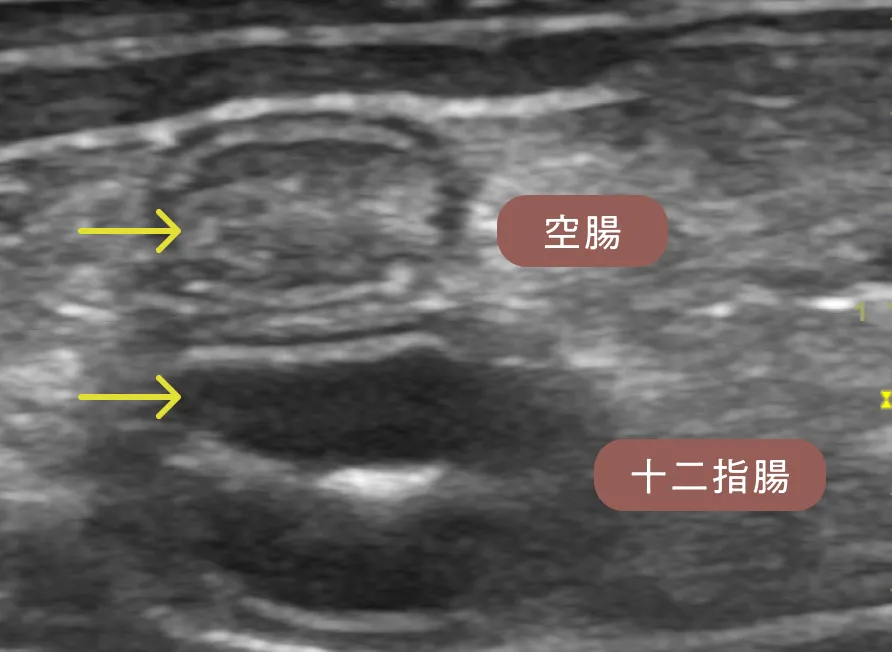

ストリエーションサインは特に空腸で重度にみられ、隣に描出した十二指腸の粘膜層(黒く分厚い層)と比較してかなり白く見えます(黄矢印)。各検査から可能性のある病気を除外し、蛋白漏出性腸症を強く疑いました。全身状態も悪くないため、ご家族と相談し、内視鏡検査を行う前にまずは食事療法の反応性を確認します。